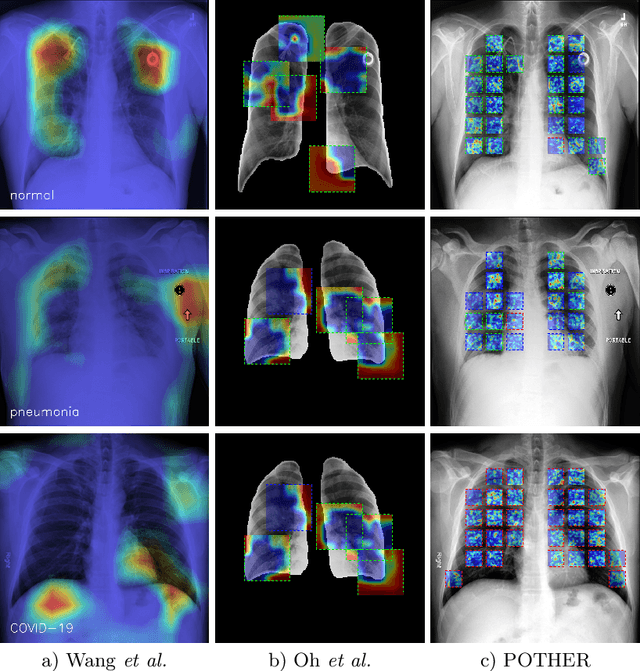

Abstract:A critical step in the fight against COVID-19, which continues to have a catastrophic impact on peoples lives, is the effective screening of patients presented in the clinics with severe COVID-19 symptoms. Chest radiography is one of the promising screening approaches. Many studies reported detecting COVID-19 in chest X-rays accurately using deep learning. A serious limitation of many published approaches is insufficient attention paid to explaining decisions made by deep learning models. Using explainable artificial intelligence methods, we demonstrate that model decisions may rely on confounding factors rather than medical pathology. After an analysis of potential confounding factors found on chest X-ray images, we propose a novel method to minimise their negative impact. We show that our proposed method is more robust than previous attempts to counter confounding factors such as ECG leads in chest X-rays that often influence model classification decisions. In addition to being robust, our method achieves results comparable to the state-of-the-art. The source code and pre-trained weights are publicly available (https://github.com/tomek1911/POTHER).